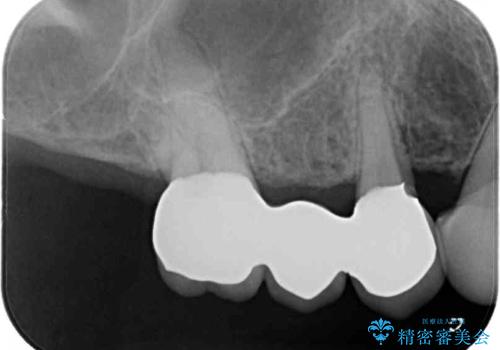

治療開始の日に欠損部も含めて仮歯が装着され、今までの不具合や不快感があっという間に改善されました。

抜歯部位の治癒を待つために時間がかかりましたが、来院回数は数回で済み、患者様には大変満足していただきました。